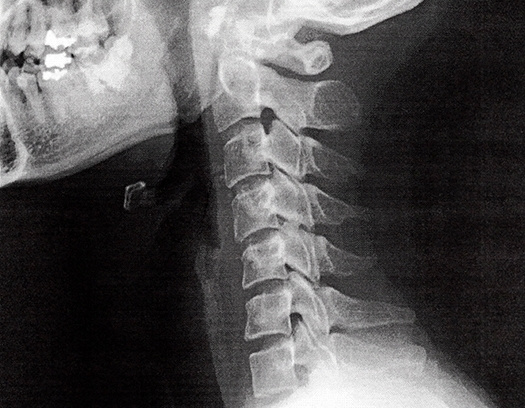

頚は、頚椎と呼ばれる7つの骨により構成されています。

椎間板の変性や靭帯が厚く硬くなることなどにより、頚部の痛みなどの症状が発現したものを総称して、頚椎症と呼んでいます。

整形外科などで、MRIやレントゲンを撮ると骨の位置異常が確認される場合があります。

MRIやレントゲンでは筋肉の硬さは映らず画像診断ではしびれの原因がわからないことがほとんどです。